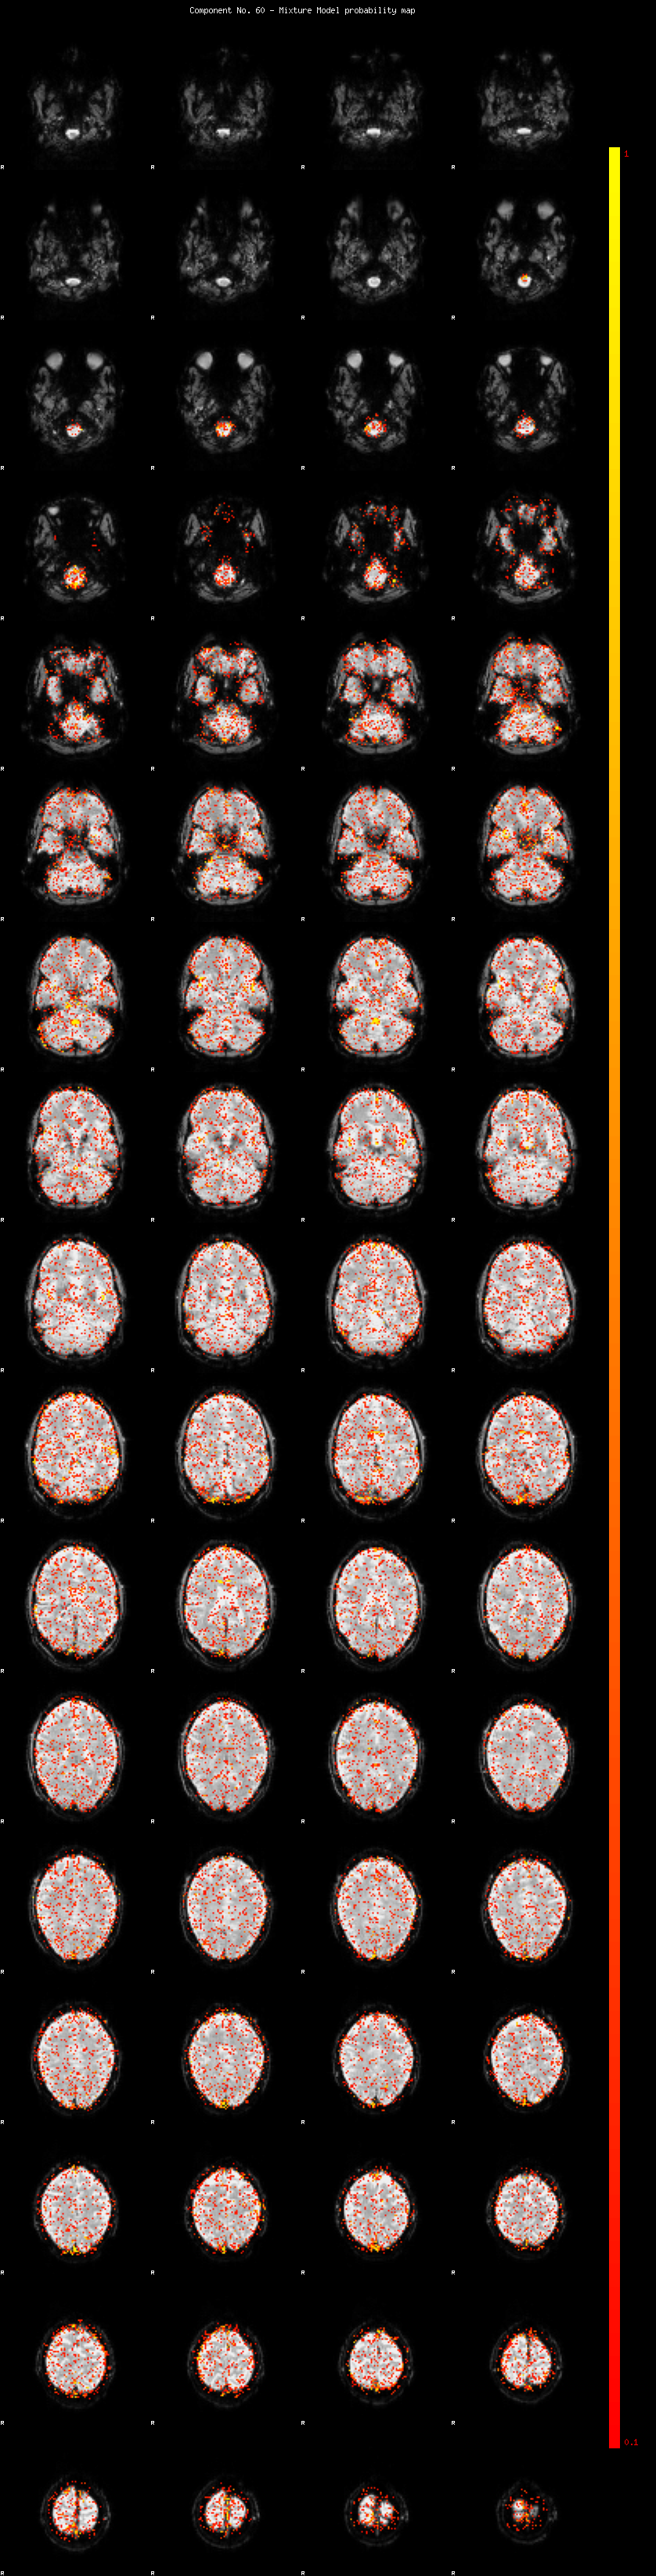

IC_60 Mixture Model fit

Means : -0.000000 2.124275 -2.074611

Vars : 1.000000 0.976137 0.854406

Prop. : 0.940605 0.034981 0.024414